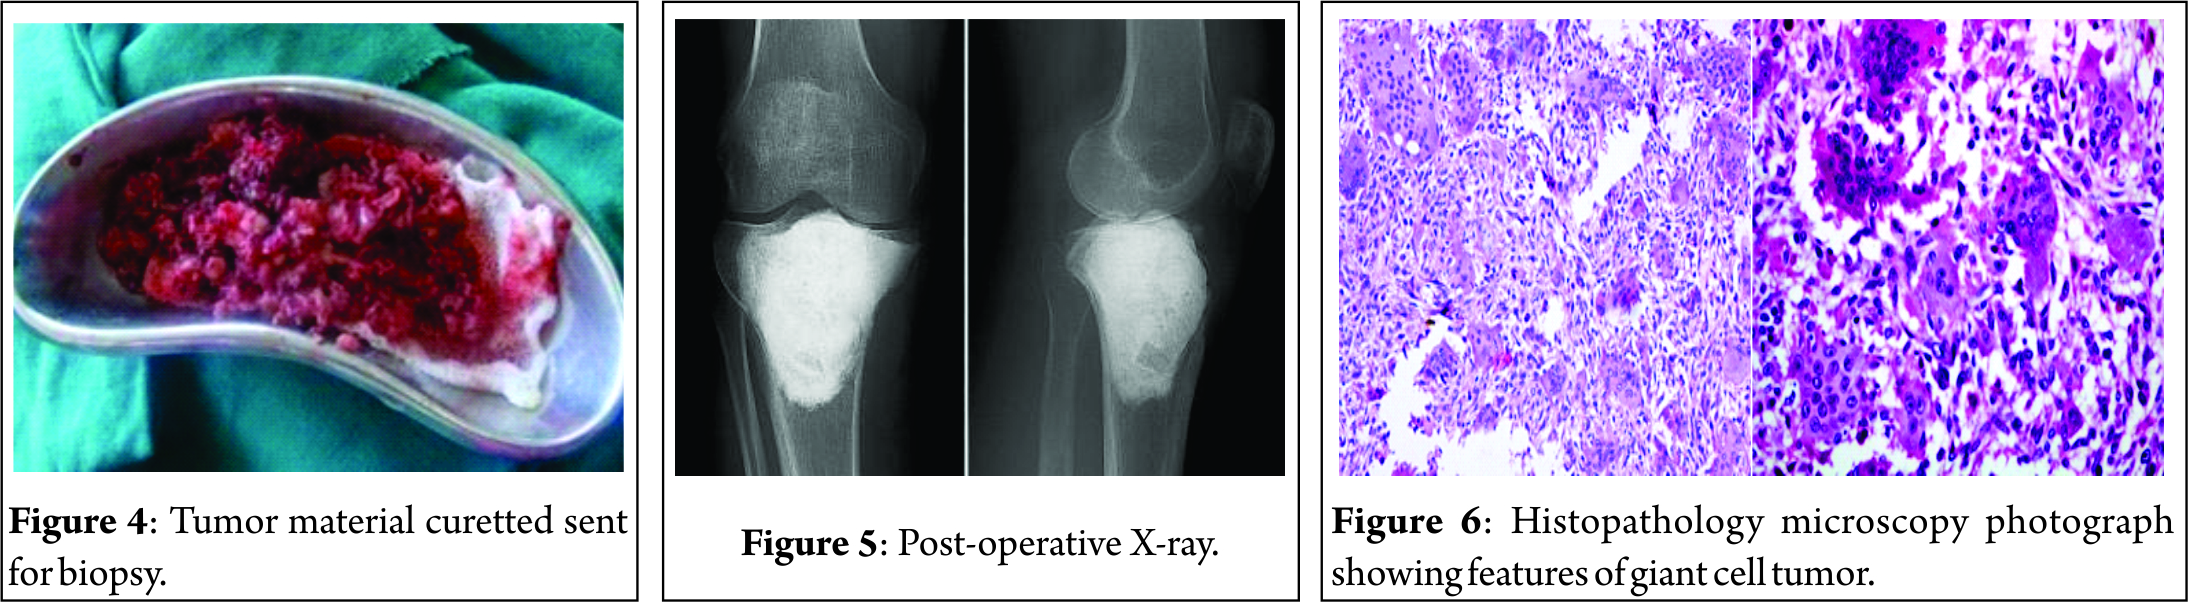

An anterolateral approach to the proximal tibia was chosen for this patient keeping the possibility of knee joint involvement in mind. The iliotibial band was incised, and the proximal tibia explored to delineate the boundaries of the lesion. The lateral cortex of the proximal tibia was nibbled out to enter the cavity (Fig. 3). A thorough curettage was done using a bone gouge. The cavity was washed with hydrogen peroxide repeatedly to induce thermal necrosis of the remnant tumor cells. A final curettage of the inner margins was done using a burr. Subchondral bone was observed to be normal, and hence, joint was preserved. The cavity was washed again with hydrogen peroxide, and antibiotic-coated bone cement was used to fill up the entire dead space in the cavity. Once the cement was set, a local wound wash was given at the incision site and wound closed in layers. The curetted material was sent for histopathological studies(Fig. 4).

Post-operative radiographs confirmed that the cavity had been completely packed with cement and no dead space was evident (Fig. 5). The post-operative period was uneventful. Weight-bearing was initiated 10 days after surgery. She achieved full range of motion of her knee joint in 3 weeks.

Histopathology

Multiple sections showed many multinucleated osteoclast-like giant cells, uniformly distributed in sheets of spindle to polygonal cells. There was no cellular atypia. Spindle-shaped tumor cells were seen having elongated ovoid nuclei with bland nuclear chromatin and scant to moderate amount of amphophilic cytoplasm. Features were strongly suggestive of GCT (Fig. 6).